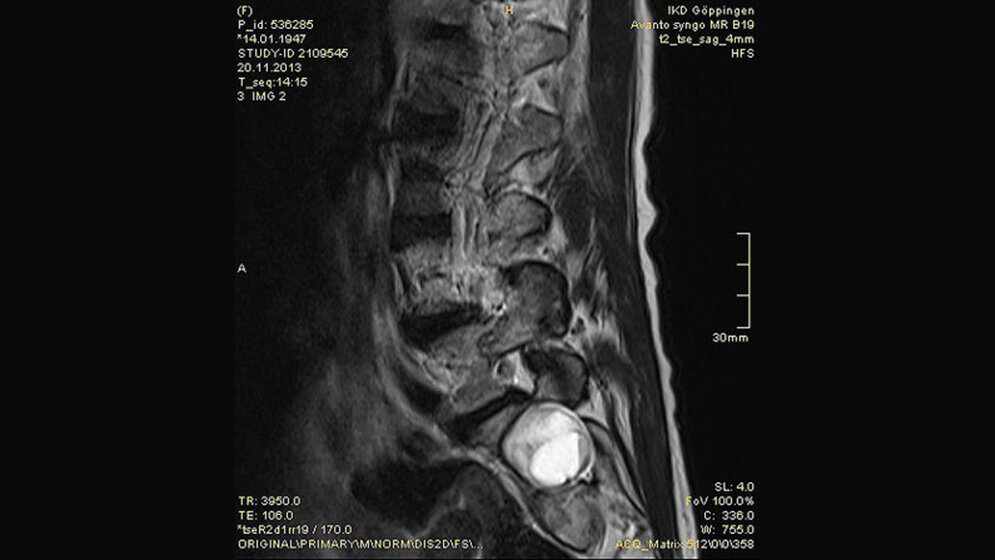

Tumoröse Veränderungen: Aneurysmatische Knochenzyste

Aneurysmatische Knochenzysten sind seltene, gutartige und lokal destruierende Knochentumoren. Es gibt typische makroskopische, histologische und bildgebende Veränderungen. Die Prognose ist von bestimmten Wachstumsfaktoren der Läsion abhängig.